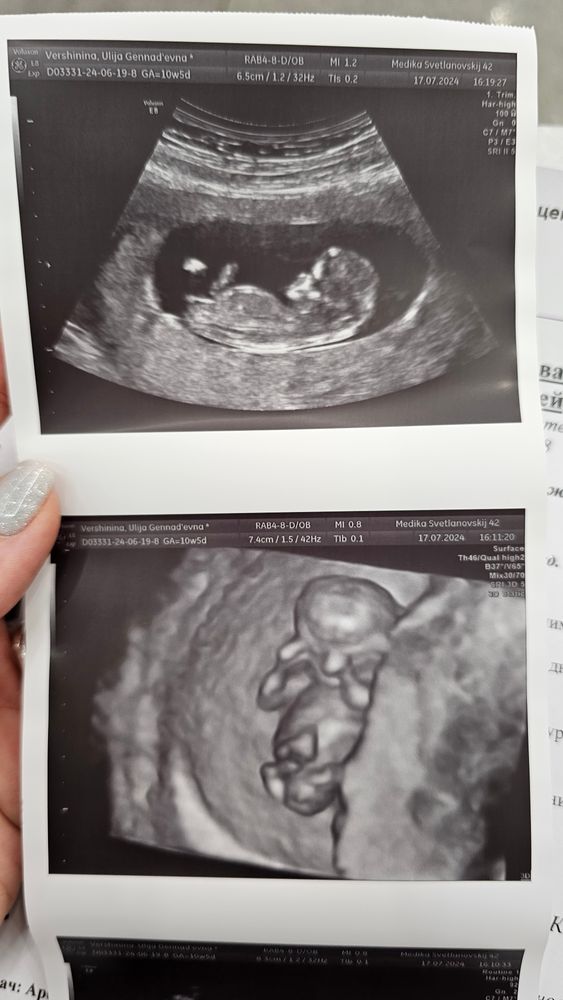

Мальчик или девочка?

Девочка 🥰 У меня 2 таких фотографии есть ☺️

Алёна, в домике третий мальчик)

На таком сроке у них одинаковый половой бугорок, только у мальчика торчит , а у девочки лежит) наклон важен.. по фото прям девочка стопроцентная 🩷👼🏼

Если смотреть по углу наклона полового бугорка то скорее всего девочка))

Узи 10н5д Фетальный допплер